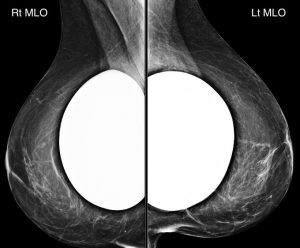

A 50-year-old woman presents for a screening mammogram:

What kind of implants are present?

B. Silicone implants

Explanation: The extremely high and homogenous density of these implants indicates that they are composed of silicone.

With saline implants, we should be able to see “through” and identify the implant valves.